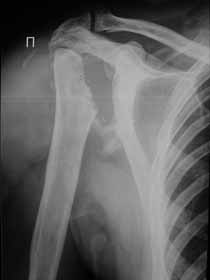

Поэтому желательно выставить все рентгенологические и данные МРТ для сравнения со снимками из статьи.

Думаю, коллеги будут не против увидеть рентген.

Извиняюсь, что-то фотографии сразу не прошли. сейчас исправимся.